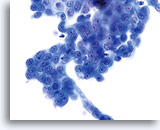

En raison de leur morphologie, les cellules issues de lésions de bas grade comptent parmi les anomalies intra-épithéliales les plus faciles à localiser et à identifier. En comparaison, les noyaux LSIL sont les plus grands et présentent un rapport N/C inférieur aux HSIL ou carcinomes. Ces cellules affichent une atypie nucléaire plus importante que les ASCUS (ce qui se traduit par une augmentation de la taille nucléaire, une irrégularité de la chromatine et une irrégularité de l’enveloppe nucléaire). Les noyaux peuvent occasionnellement ne pas être aussi hyperchromatiques que sur les frottis conventionnels, mais ils le sont toujours par rapport aux cellules normales environnantes. Les changements associés au HPV (par exemple, formation de cavités dans le cytoplasme) sont plus évidents grâce à la fixation liquide et à la technique de transfert, ce qui élimine la déformation des cellules associée à la méthode d’étalement conventionnelle. La méthode ThinPrep préserve mieux ces changements cellulaires, ce qui permet une meilleure distinction entre les véritables cavités cytoplasmiques induites par le HPV et les vacuoles bénignes/dégénératives et/ou les cellules malpighiennes glycogénées.

Comme il s’agit de cellules malpighiennes matures, elles gardent leur forme polygonale et conservent en partie leur taille normale. La taille des noyaux est au moins 3 à 4 fois supérieure à celle d’une cellule intermédiaire normale. En revanche, quand les changements associés au HPV sont évidents, les cellules peuvent être plus petites (quasiment parakératosiques), tout comme les noyaux (quelque peu pycnotiques) qui présentent en outre une binucléation et/ou multinucléation. Ces noyaux pycnotiques affichent en outre des caractéristiques anormales : hyperchromasie, augmentation de la taille par rapport à une cellule malpighienne superficielle normale, légère variation de la forme et de la taille, etc. Il est important d’insister sur le fait qu’une interprétation de LSIL/HPV implique des cavités cytoplasmiques nettes accompagnées de la morphologie nucléaire anormale décrite ci-dessus.